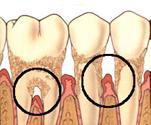

În ultimii 25 de ani s-au înregistrat progrese remarcabile în tratamentul parodontopatiilor marginale mai ales în zona regenerarii parodontale si osoase, teorie sustinuta de ipoteza conform careia celulele progenitoare din ligamentele parodontale sunt capabile sa regenereze sistemul ligamentar de sustinere parodontala (Melcher - 1976).

Majoritatea tratamentelor care aveau la baza aceasta ipoteza foloseau membrane-bariera pentru regenerarea tisulara dirijata (guided tissue regeneration - GTR) cu rol de a selecta si spori anumite populatii celulare si de a stimula apozitia coronara de ligamente si de cement pe suprafetele radiculare denudate. Ulterior, utilizarea grefelor os 24524m1214y oase (autogrefe, alogrefe, xenogrefe) si a conditionarii suprafetei radiculare cu acid citric a adus noi evidente histologice în explicarea procesului de regenerare tisulara. Vindecarea plagilor parodontale dupa aceste procedee este de tipul noii insertii si nu prin regenerare parodontala (vezi tabel).

S-a demonstrat ca proteinele cu origine în teaca radiculara Hertwig au un rol crucial în formarea cementului radicular acelular din cursul dezvoltarii radacinii dentare. Aceste proteine accelereaza formarea de ligamente parodontale si os alveolar în cursul embriogenezei. De aceea, administrarea de astfel de proteine exogene care se regasesc si în matricea smaltului dentar, ar avea un efect terapeutic regenerativ.